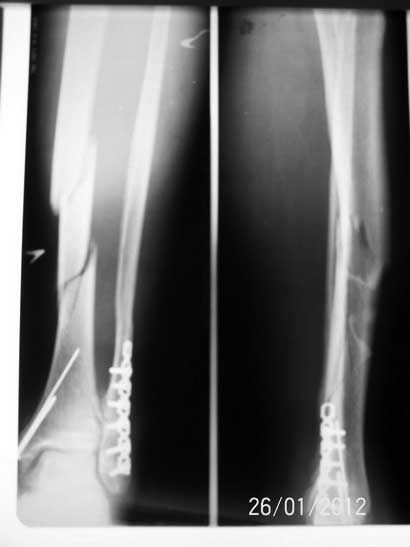

[Ortho] Фрагментарный перелом большеберцовой кости

Уважаемые коллеги! Пациент 48-ми лет. Травма в результате падения с высоты собственного

роста. В анамнезе 2 года назад перелом нарудной и внутренней лодыжек - остеосинтез, в течение

полугода периодически лигатурные свищи в области наружной лодыжки, лигатурный свищ при

поступлении. На наш взгляд БИОС в данном случае оптимален, однако появилась и

противоположная точка зрения - о необходимости открытой репозиции и синтеза пластиной.

Появятся ли сторонники ORIF, и если можно с аргументацией преимущества метода. Ждем ваших

мнений.